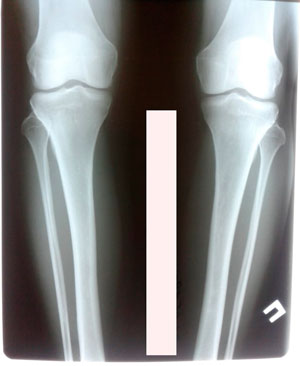

на фиксации

IMG_3925-30-06-19-08-20.JPG

IMG_3932-30-06-19-08-20.JPG